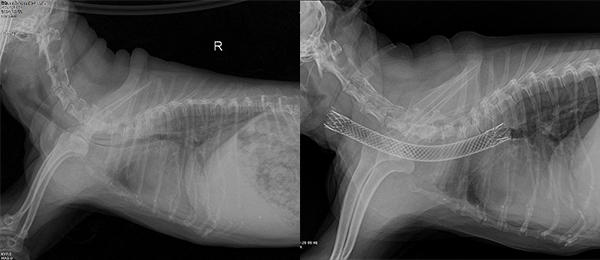

3. 호흡기계 중재치료

내과적 치료로 관리가 가능한 기관 허탈에서 심화된 기관 협착의 정도가 심해지면 기침, 과호홉, 좌위호흡 등 호흡곤란과 청색증을 보입니다. 이러한 환자들에게 호흡을 위한 공간을 만들어주기 위해 기관에 스텐트를 삽입하여 기관을 확장하는 시술을 합니다. 본원에서는 대부분의 환자에게 적용 가능한 강아지 기관 전용 스텐트를 사용하며 숙련된 전문의가 시술을 진행합니다.